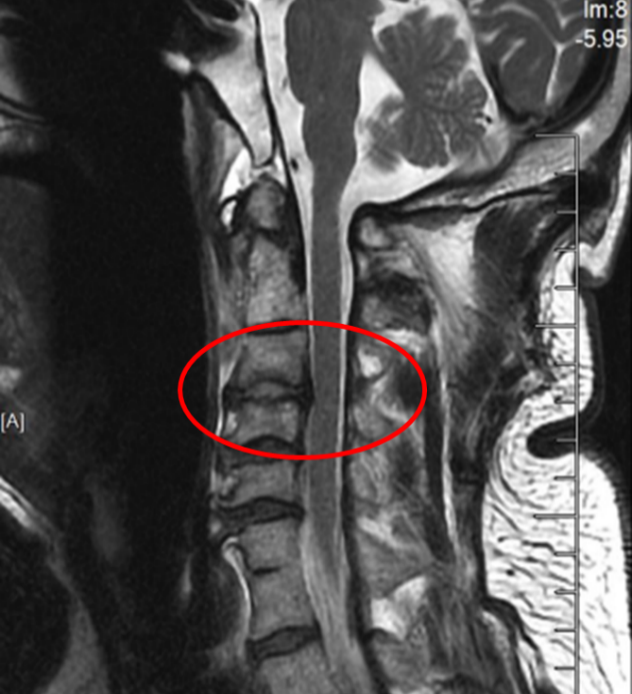

图2:术后正侧位片

此次手术的成功凝聚了苏大附四院脊柱外科团队多年来在上颈椎领域的深耕细作,是“微创理念”与“智能科技”完美融合的典范。特别是姜为民主任专利研发的新型齿状突螺钉,通过小切口实现了传统开放手术难以企及的精准与安全,兼具微创与稳固的双重优势,为此类疾患治疗带来更佳的方案选择。